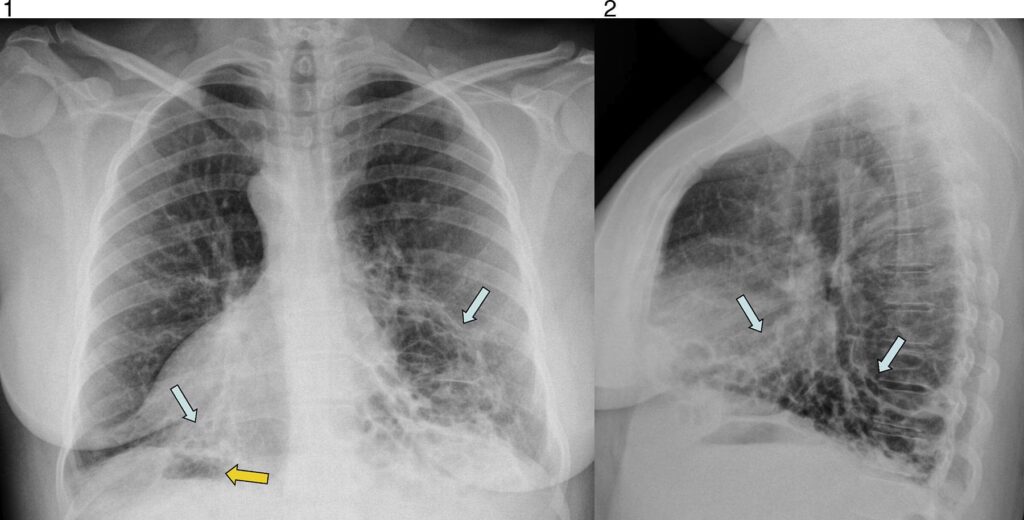

- Bronquiectasias: Dilataciones anormales e irreversibles de los bronquios, que dificultan la eliminación de secreciones y aumentan el riesgo de infecciones recurrentes y daño pulmonar progresivo.

El diagnóstico del Síndrome de Kartagener puede ser un desafío debido a su rareza y a la superposición de síntomas con otras enfermedades respiratorias crónicas, como la fibrosis quística o el asma. La sospecha clínica es crucial, especialmente ante la presencia de infecciones respiratorias recurrentes, bronquiectasias inexplicables y, sobre todo, el hallazgo de situs inversus.

- Tomografía Computarizada (TC) de alta resolución anual o periódica para evaluar la extensión y progresión de las bronquiectasias.